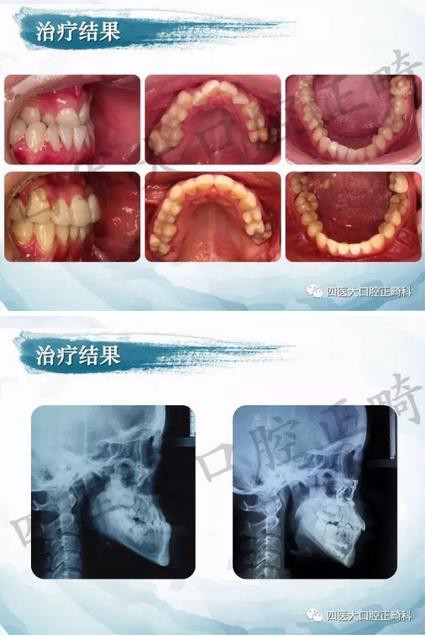

相關(guān)正畸矯正